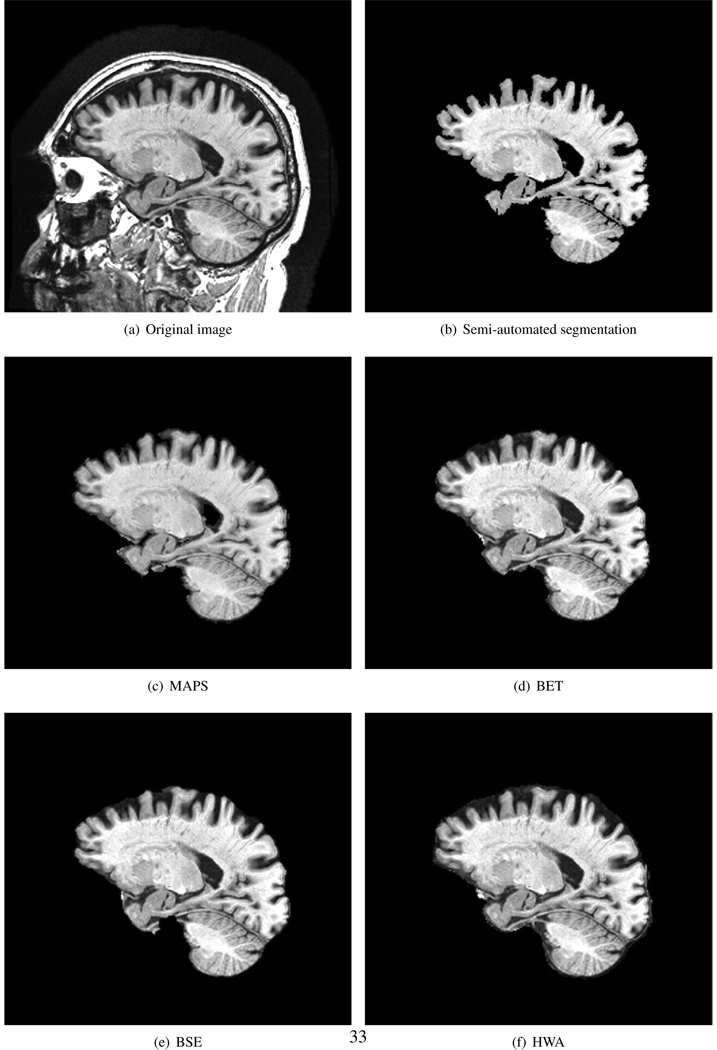

Typical performance of automated brain extraction methods in 1.5T and 3T scans in our dataset are shown in Figs. 4 and 6. In addition, Figs. 5 and 7 show examples of thresholded segmentations using 60% of the mean intensity of the semi-automated segmentation in 1.5T and 3T scans. Tables 5 and 6 show the median and CR (1st-99th centile range) of the Jaccard index, false positive rate and false negative rate of MAPS, BET, BSE and HWA using the 1.5T and 3T scans respectively. MAPS had the highest median Jaccard index, and BSE had the lowest median false positive rate. HWA, closely followed by MAPS, had the lowest median false negative rate. Furthermore, MAPS had the smallest CR in the Jaccard index, false positive rate and false negative rate. We found that while no MAPS and HWA segmentations failed, 2 BET segmentations (2 1.5T images) and 3 BSE segmentations (2 1.5T and 1 3T images) failed (see Fig. S.1(a) and S.1(b) in the supplementary material for two examples).

Figure 4.

Examples of whole brain extraction results of MAPS, BET, BSE and HWA of a 1.5T scan (ADNI subject ID: 126 S 0680). While all techniques had some errors in including non-brain (e.g. dura) voxels in some areas – the amount varied between methods (arrows).